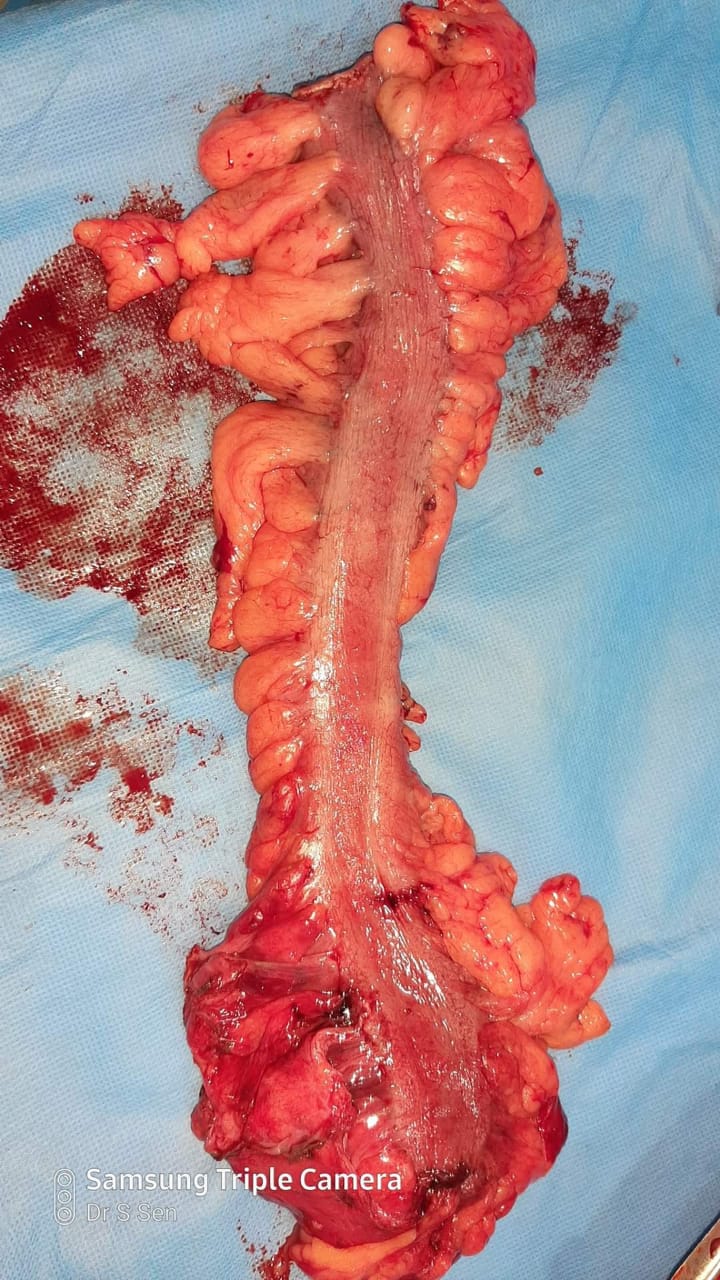

A Young lady who was a small kid...when her mother was operated for a Complex Gastrointestinal condition almost 14 years back by Dr Suddhasattwa Sen suddenly came in with severe blood loss from Gastrointestinal tract with a loss of almost 2 to 3 litres of blood with Shock with fainting . Further stabilisation was done and then extensive investigation revealed not only Piles and GI Ulcers but also SRUS Bleeding ulcers in rectum. A condition called Solitary Rectal Ulcer Syndrome ( a complex and difficult to cure anorectal problem ) . Her hemoglobin dropped to below 7 gm% She finally underwent surgery after 5 days and left home after 2 days post op without any further bleed or problems .